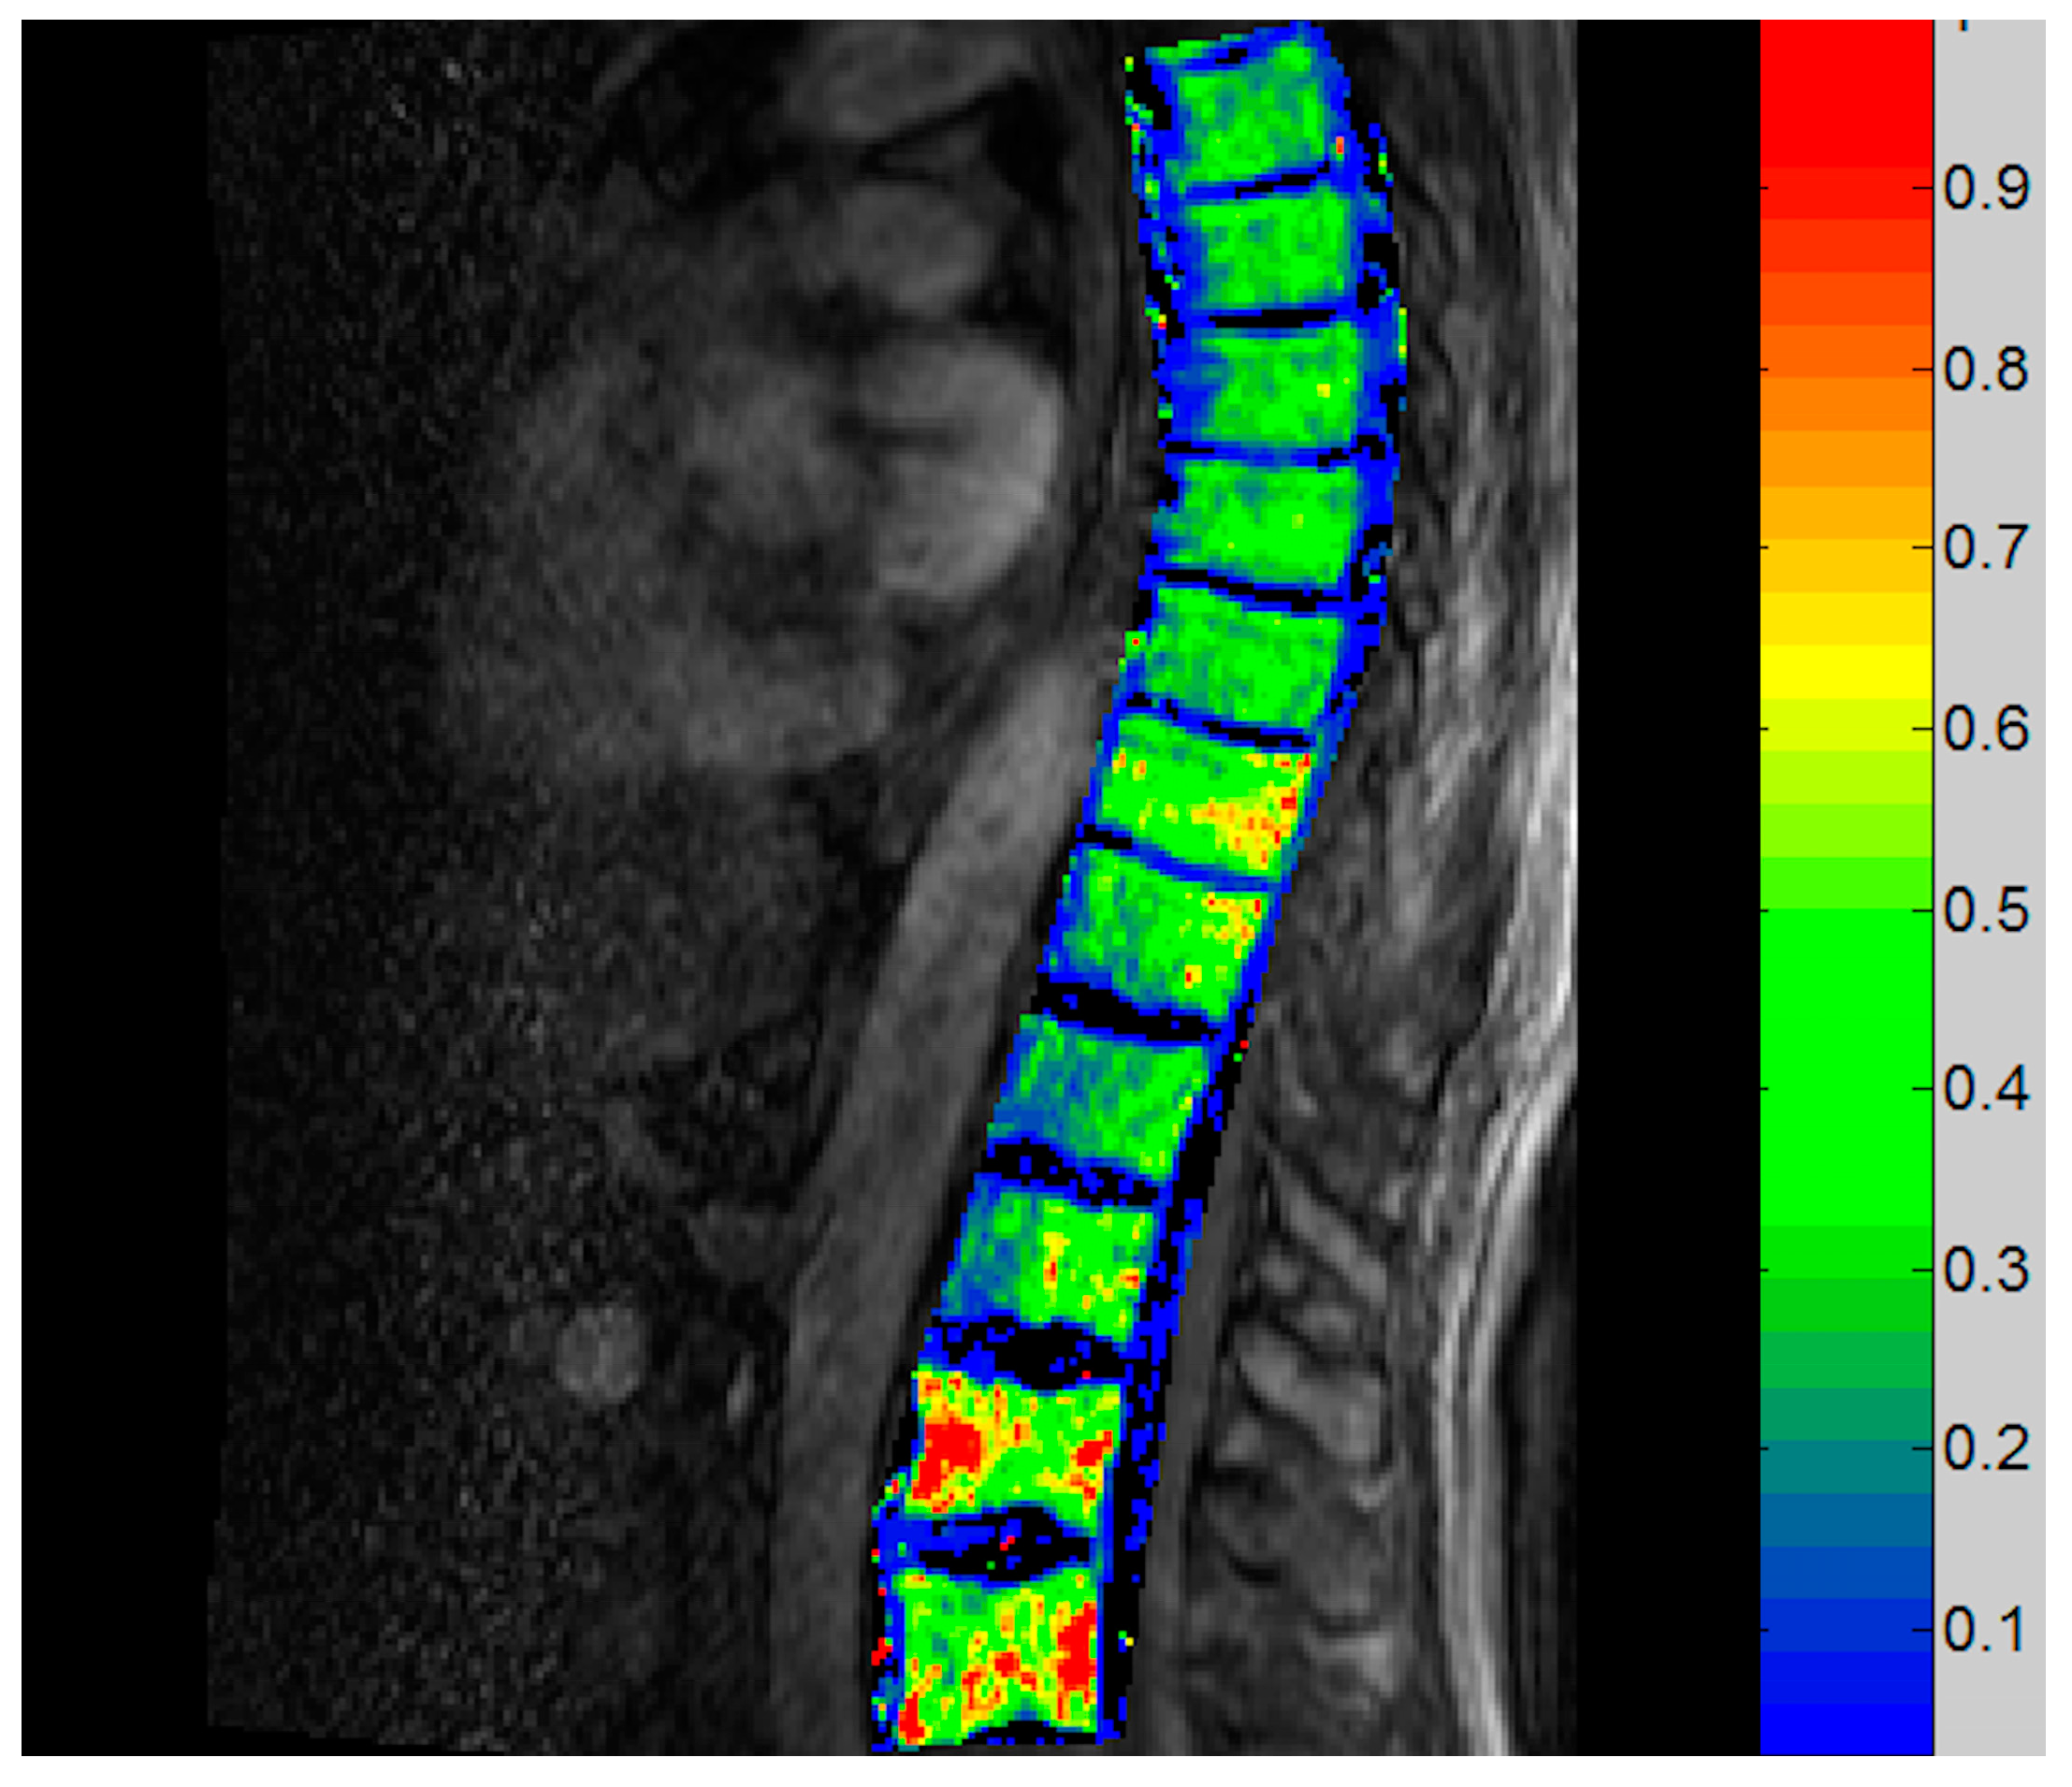

3.3.3. Vertebral DCE-MRI

| DCE-MRI | Th 7/9, L1 | Ktrans, Ve, Kep |

| MRI T1 a | Dixon Fat–Water Signal Ratio b | DCE-MRI c (Spine) | 15O-Water PET Flow d (Spine) | 18F-NaF PET SUVintegral e | |||||

|---|---|---|---|---|---|---|---|---|---|

| Pelvis | Spine | Pelvis | Spine | Ve | Ktrans | Pelvis | Spine | ||

| Pt 3 | |||||||||

| T0 | 1P | 1H | 0.5 (–) | 0.22 (–) | - | - | 0.37 (–) | 0.11 (–) | 0.09 (–) |

| T6 | 2P | 1P | 1.14 (+128%) | 0.28 (+27%) | +11% | +1% | 0.45 (+22%) | 0.12 (+9%) | 0.09 (=) |

| T18 | 2P | 1P | 1.12 (+124%) | 0.16 −27%) | −1% | −13% | 0.54 (+46%) | - | 0.08 (−11%) |

| Pt 4 | |||||||||

| T0 | 1H | 0H | 0.77 (–) | 0.34 (–) | - | - | 0.61 (–) | 0.14 (–) | 0.22 (–) |

| T6 | 1H | 0H | 1.44 (+87%) | 0.76 (+124%) | +33% | +34% | 0.63 (+3%) | 0.17 (+21%) | 0.23 (+5%) |

| T18 | 1H | 0H | 1.34 (+74%) | 0.48 (+41%) | +153% | +185% | 0.66 (+8%) | 0.13 (−7%) | 0.20 (−11%) |